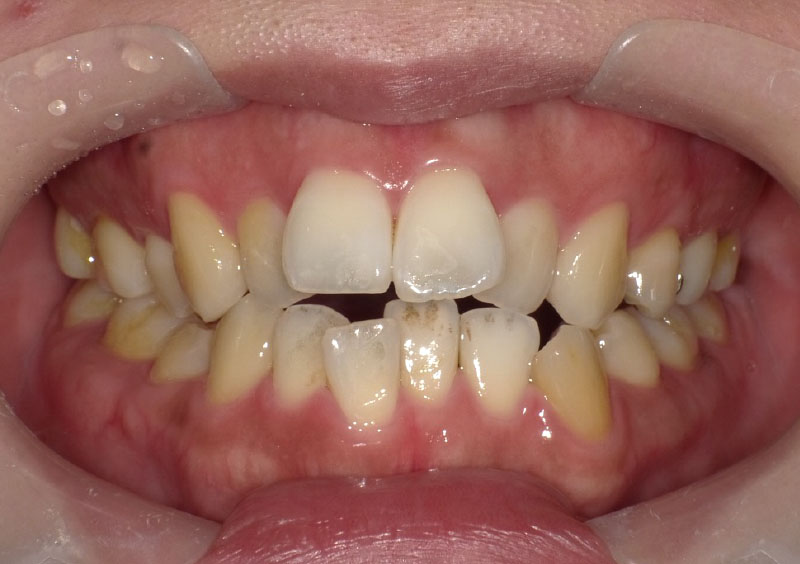

治療前

主訴 | 前歯がガタガタ、 スペース不足で今後が不安。 |

---|---|

治療期間 | 2年間 |

治療費 | ¥190,000(税込) |

治療内容 | 上下顎に床矯正装置を使用。 上顎のみ、装置を追加し、 合計3装置使用。 |

治療のリスク | 小学校低学年での治療開始であり、 装置の使用、管理にリスクがあったが 本人、家族の協力もあり予定期間での 改善が得られた。 |